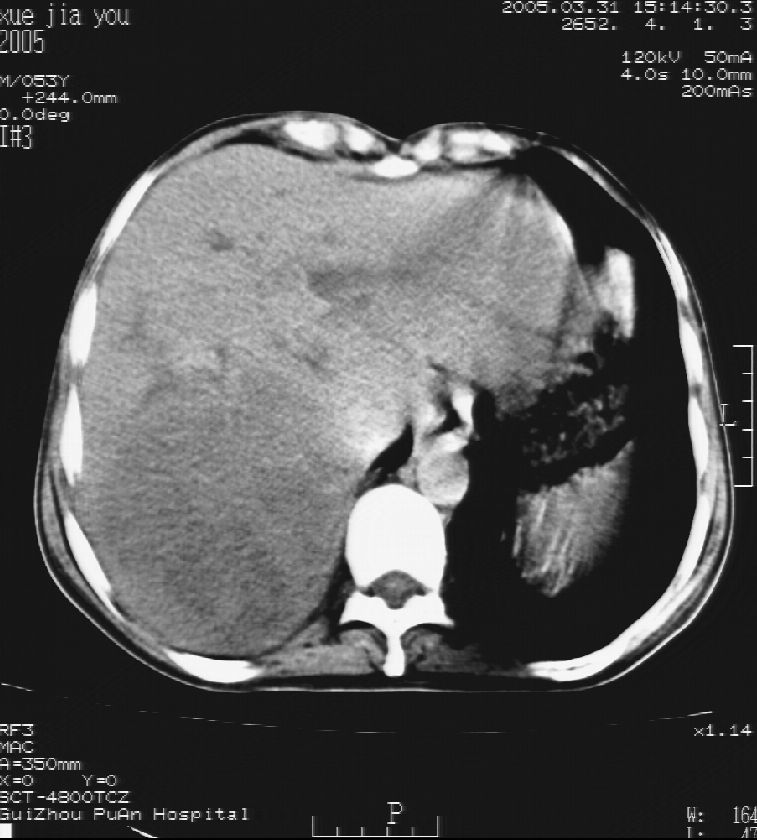

男 55岁  反复上腹痛1年,伴恶心呕吐。2005年做第一次检查后,到外院做b超检查提示肝囊肿,未做任何手术。2006年做过胆总管结石术。骨窗未见异常

这个病灶很有意思,怎么可能没有了呢?我考虑当时很可能是肝脏脓肿(b超示囊肿是有可能误诊的,因为影像表现都是低回声吗?),现在脓肿吸收了,肝脏萎缩,肝裂增宽了.别的肝叶代偿增大,不过现在左内叶的确有个占位,肝内多发结石,脾脏比以前大,不排除有肝硬化可能.建议增强扫描给于定性!!!!

肝硬化\\脾大,肝左叶肝癌可能性大,建议增强扫描.肝内胆管多发性结石.

1, 肝硬化,脾大;2,肝左叶肝癌可能性大,建议增强扫描.3,肝内胆管多发性结石.

考虑肝内胆管多发结石引起的肝内局部炎症,这样可以解释2005年肝右叶病灶的吸收和左叶新病灶.

肝硬化、脾大、肝内胆管多发结石。肝左叶低密度占位。建议增强扫描.排除肝癌